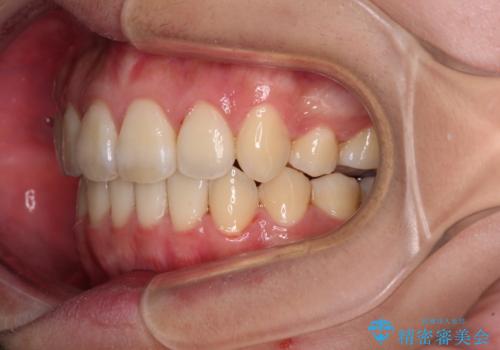

- 八重歯と叢生を気にして来院された患者様です。

上下の前歯が非接触であり、叢生や八重歯が顕著であったため、上顎左右第一小臼歯2本を抜歯して排列することとしました。

抜歯により移動量が多くなるため、ワイヤーや補助装置を活用し、その後インビザラインによる矯正治療を行うこととしました。

元々奥歯に負担のかかる咬み合わせですり減っていたため、仕上がった歯並びでも奥歯が咬んでいないように見えましたが、実際にはしっかりと咬合しており、患者様本人も咬んだ感触に違和感はないとのことでした。